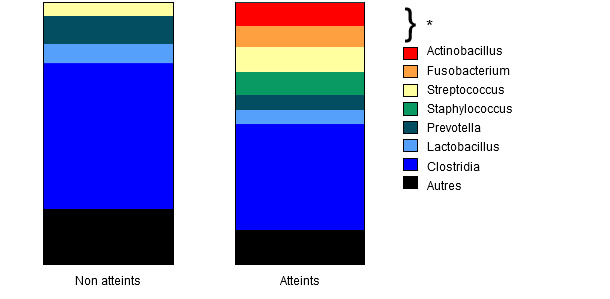

La détection des gènes de la toxine exfoliative de Staphylococcus hyicus par PCR a été négative même si la PCR était plus optimisée pour les extraits de culture que pour les extraits générés à partir d’échantillons de tissu (Onuma, Uoya et al.2001). L’analyse métagénomique de l’épiderme et du derme par amplification de la région hypervariable V3-V4 du gène bactérien 16S rRNA a révélé des différences significatives dans la diversité alfa (richesse d’espèces) (P = 0,003) entre les porcs avec une nécrose chronique et les porcs sans nécrose. Ceci signifie que le nombre d’espèces identifiées, selon le nombre de séquences échantillonnées dans chaque groupe, a été plus faible dans le groupe chronique. Concrètement, l’abondance relative d’ Actinobacillus spp., Fusobacterium spp., Streptococcus spp. et Staphylococcus spp. a été significativement différente entre les groupes atteints (en combinant les aigus et les chroniques) et les non atteints (figure 6).

Figure 6 : abondance relative dans chaque groupe de différents genres de bactéries et de la classe Clostridia.

On a utilisé une analyse statistique pour estimer l’importance biologique de chaque taxon significatif. En comparant les porcs avec des nécroses d’oreilles (combinaison de groupes chroniques et aigus) avec des porcs sans nécrose, on a déterminé que 209 taxons avaient des différences significatives dans leur abondance alors qu’en comparant entre les aigus, les chroniques et les non affectés, les différences se limitaient à 24 taxons. A l’intérieur de ce groupe, on a identifié deux bactéries potentiellement septicémiques comme biologiquement significatives dans les prélèvements de porcs avec une affection aigüe : Actinobacillus spp. et Haemophilus spp.

Normalement dans ces cas, la présence d’inflammation dermique avec peu de changements épidermiques suggère un processus «de l’intérieur vers l’extérieur» plus qu’un processus « de l’extérieur vers l’intérieur » et pourrait suggérer une fragilisation vasculaire qui permet la colonisation et une progression de la lésion due à des bactéries opportunistes. L’analyse métagénomique a montré que les communautés bactériennes changeaient significativement au fur et à mesures que les lésions progressent ; on doit chercher davantage pour déterminer si les genres Actinobacillus et Haemophilus agissent comme étiologies primaires ou sont envahisseurs secondaires dû à la fragilisation vasculaire.